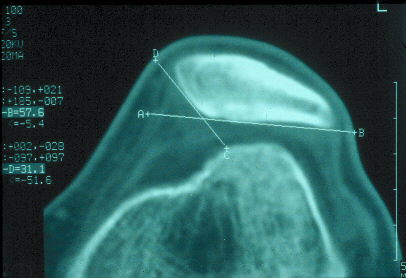

El TAC o escáner sirve para estudiar en profundidad el caso, como este que se muestra a la derecha donde se ve perfectamente la basculación de la rótula con desplazamiento externo, con lo que se encuentra subluxada o fuera del canal troclear.